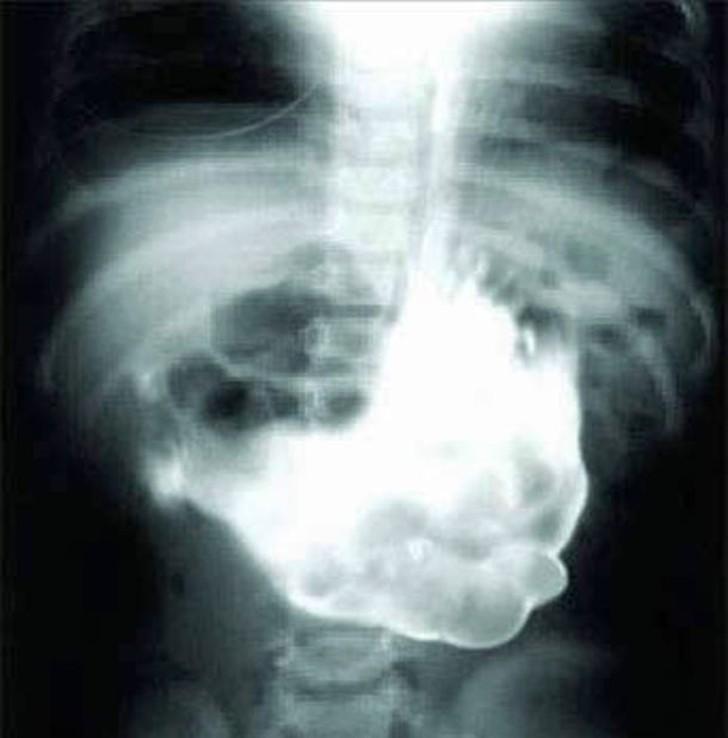

17. Огромный комок шерсти.